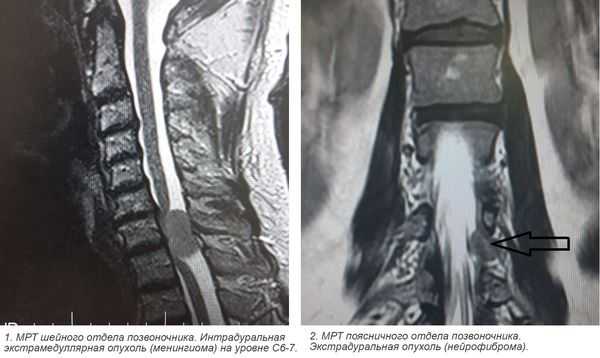

- экстрадуральная опухоль - очаг над областью твердой мозговой оболочки;

- интрадуральная - опухоль под твердой оболочкой;

- интрамедуллярная - растет внутри спинного мозга, происходя из его клеток.

- экстрамедуллярные опухоли могут быть экстрадуральными (располагаются над твёрдой мозговой оболочкой) и интрадуральными, или субдуральными (локализуются под твёрдой мозговой оболочкой).